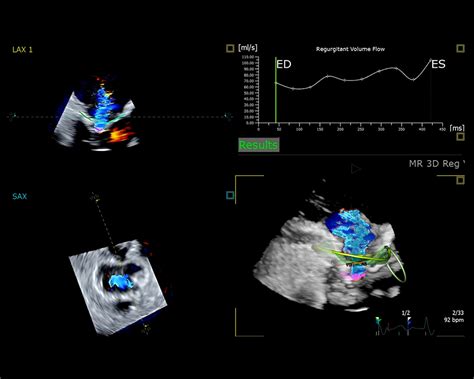

Možnosti použitia ultrazvuku sú však ešte ďaleko širšie. Jedným z posledných výdobytkov ultrazvukovej techniky je sonografia, metóda ultrazvukového zobrazovania, ktorá sa používa v lekárstve obzvlášť v gynekológii.